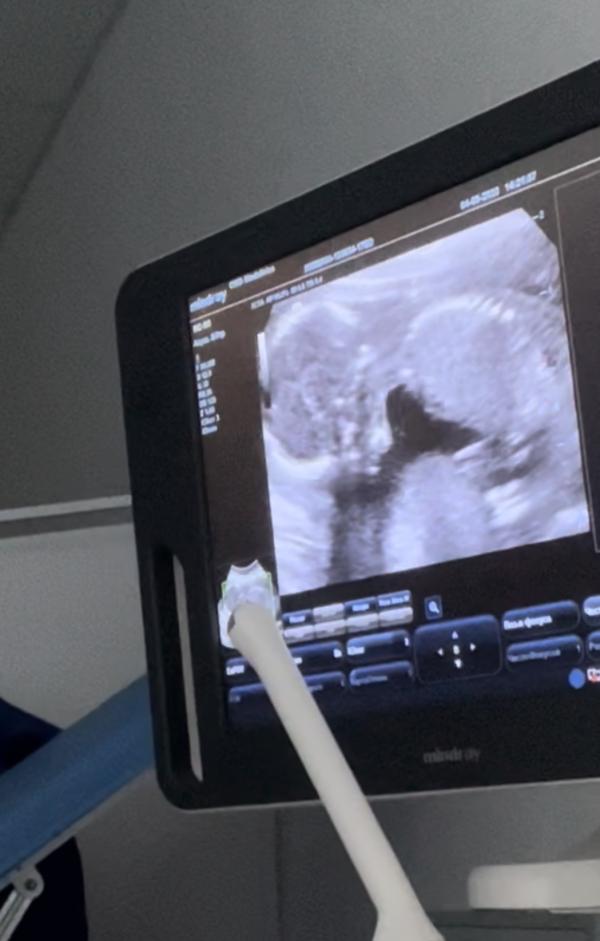

По замерам сказали примерно 20см полный рост и 215гр 💗

Девочка) посмотрите 3ю фотографию